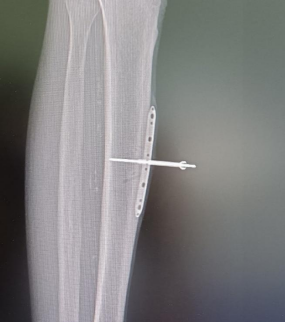

“就像树一样,没有营养供给就会坏死。坏死后如果没有及时的治疗,闭塞就会越来越严重,这名患者足的前后侧血管就出现了严重闭塞,逐渐出现坏死。” 徐楚江解释道,他考虑到患者脚趾部分已经缺血坏死,为了尽最大可能保住患者的脚掌,首先截掉患者已坏死的脚趾部分,填塞骨水泥保住剩余的皮肤,再使用骨膜牵张术逐步植入特殊器械。

骨膜牵张术后,侧肢循环建立

三周后,成功诱导下肢微血管网再生,恢复血运,避免了足部进一步坏死,保肢成功。